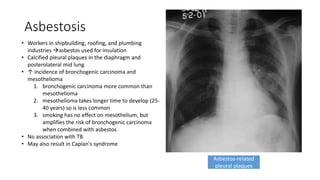

• Workers in shipbuilding, roofing, and plumbing

industries asbestos used for insulation

• Calcified pleural plaques in the diaphragm and

posterolateral mid lung

• ↑ incidence of bronchogenic carcinoma and

mesothelioma

1. bronchogenic carcinoma more common than

2. mesothelioma takes longer time to develop (25-

40 years) so is less common

3. smoking has no effect on mesothelium, but

amplifies the risk of bronchogenic carcinoma

when combined with asbestos

• No association with TB

• May also result in Caplan's syndrome

Asbestos-related

pleural plaques